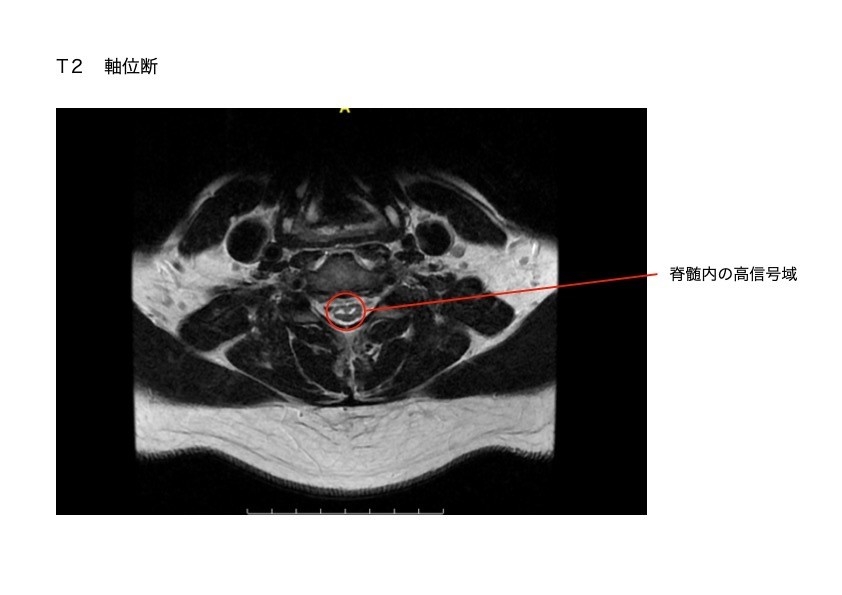

・脊髄梗塞 (前脊髄動脈症候群)

前脊髄動脈の支配領域である脊髄腹側約2/3錐体路と脊髄視床路に血流障害が生じます。

脊髄の中の動脈が血栓で詰まり、首から下の脊髄神経が壊死しました。